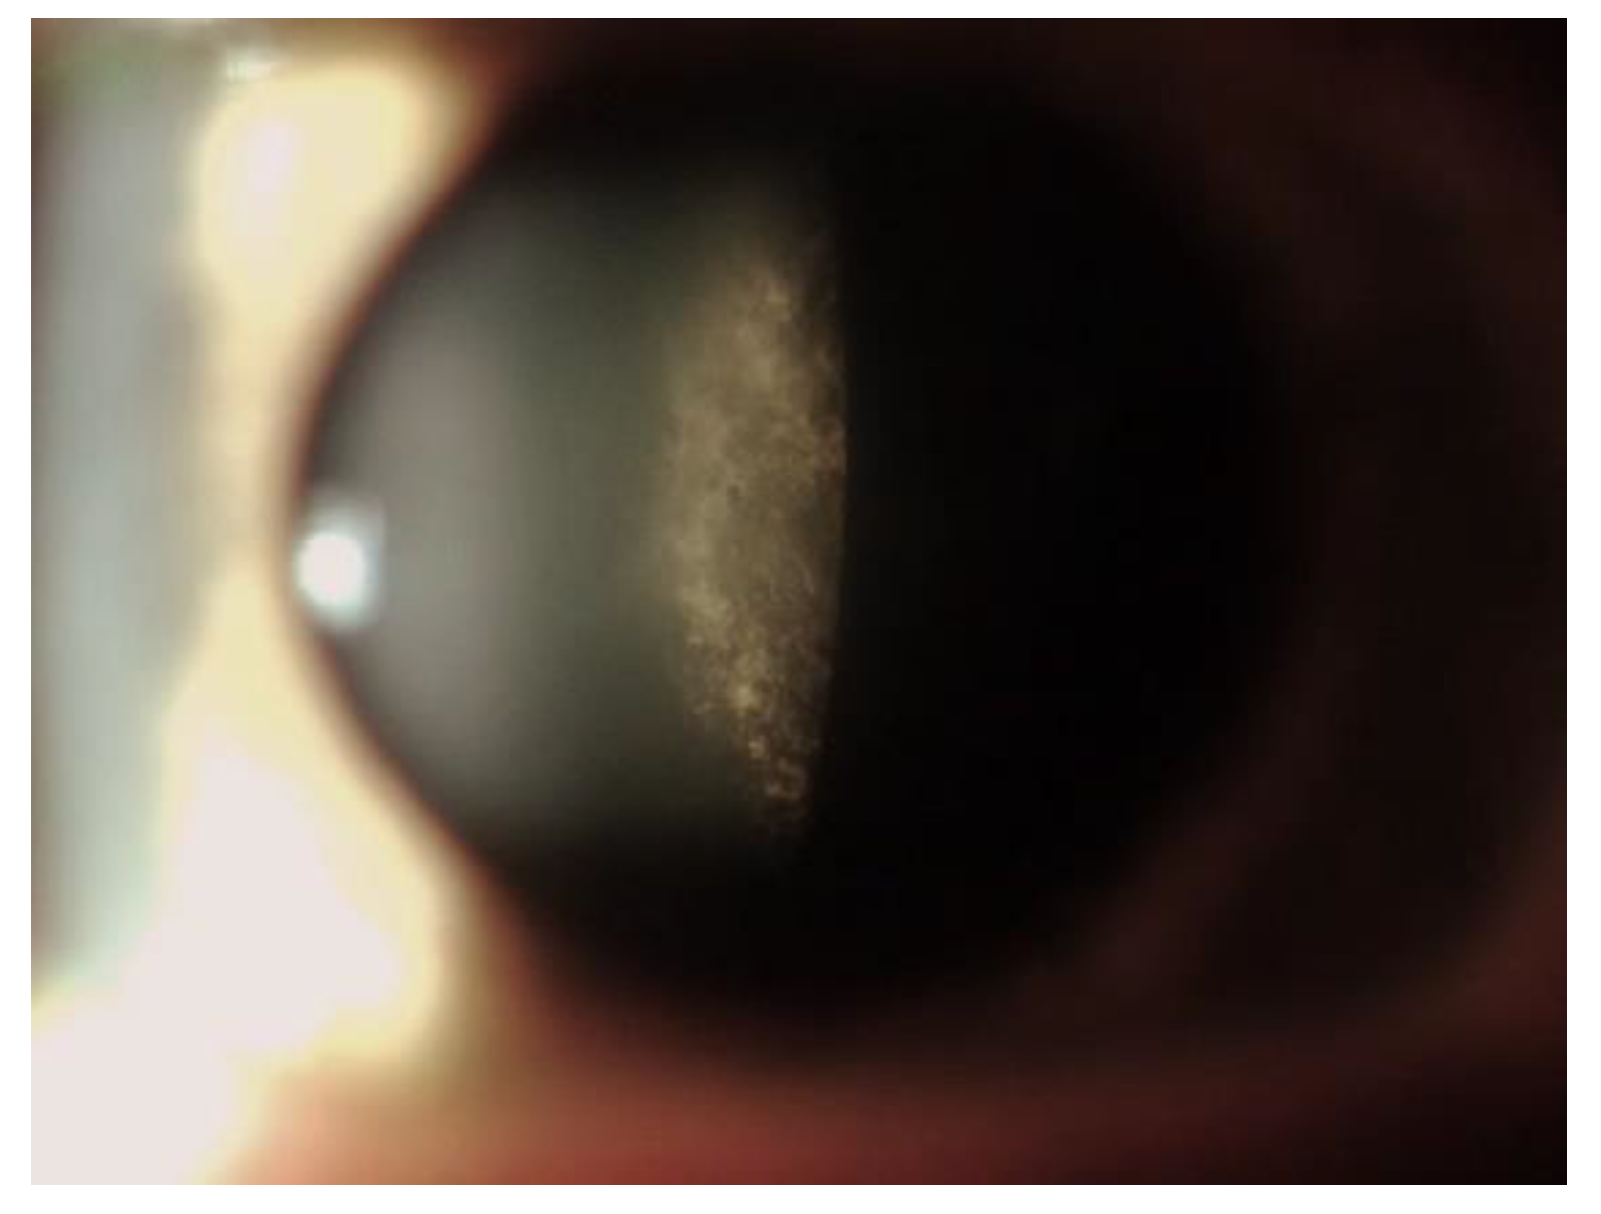

5. Corneal Manifestations

5.5. Differential Diagnosis of Vortex Keratopathy